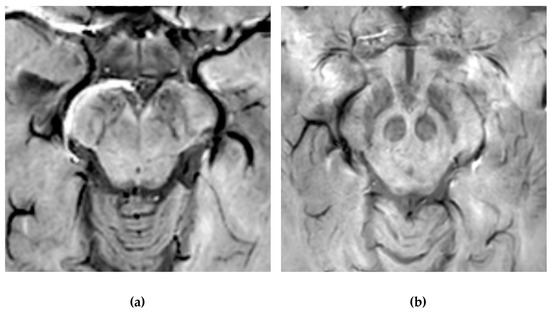

4.1. Neuromelanin Imaging